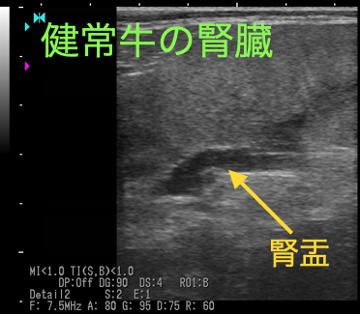

腎盂が拡張しています。右に示す他の牛と比較することでよくわかります。